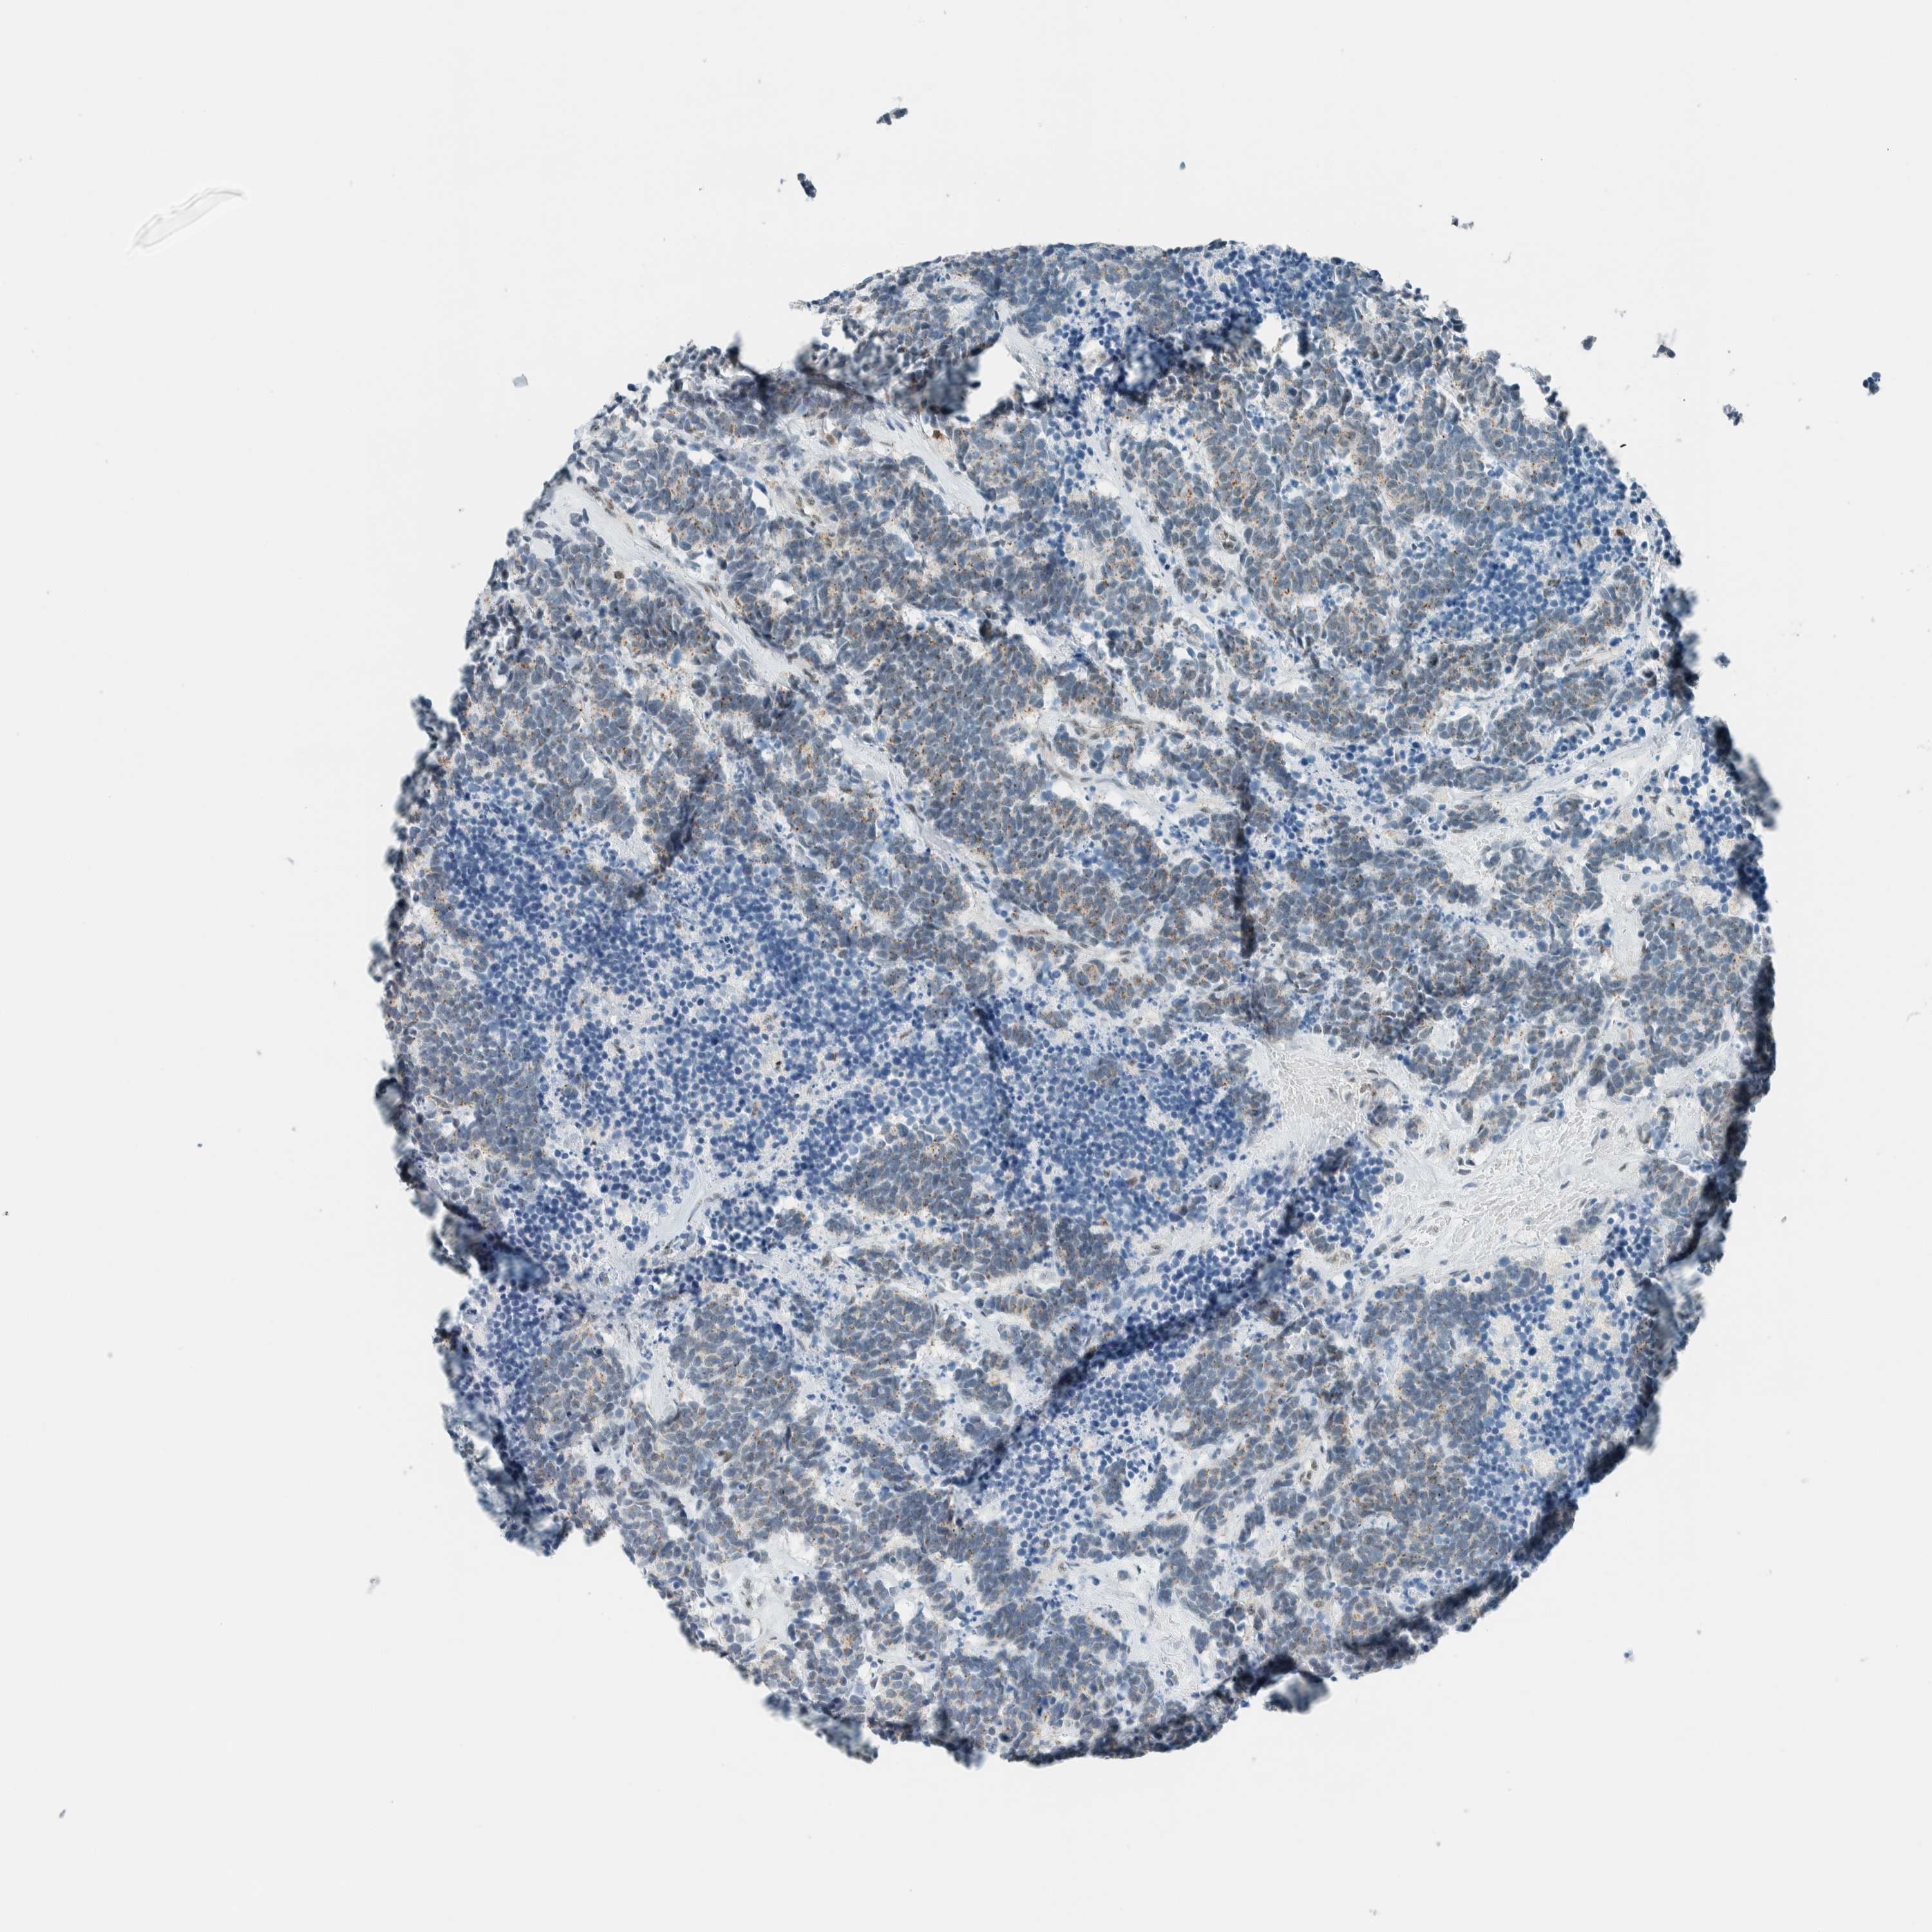

CARCINOID - Protein expressioni

A mouse-over function shows sample information and annotation data. Click on an image to view it in a full screen mode. Samples can be filtered based on level of antibody staining by selecting one or several of the following categories: high, medium, low and not detected. The assay and annotation is described here.

Each image is clickable and will lead to virtual microscopy that enables deeper exploration of all samples and also displays staining intensity scores, fraction scores and subcellular localization as well as patient and tissue information for each sample.

Antibody HPA021883

Antibody HPA021886

Staining

High

Medium

Low

Not detected

Intensity

Strong

Moderate

Weak

Negative

Quantity

>75%

75%-25%

<25%

None

Location

Nuclear

Cytoplasmic/membranous

Cytoplasmic/membranous,nuclear

Carcinoid, malignant, NOS

Carcinoma, NOS